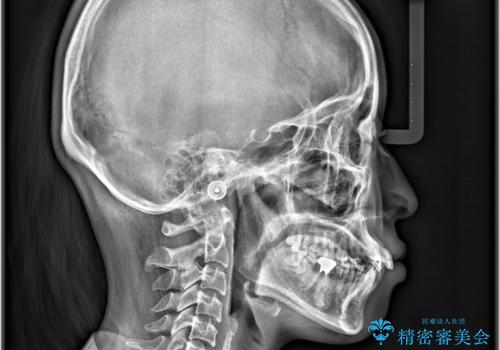

- 「歯のデコボコ、八重歯、口ボコが気になる」を主訴に来院された患者様です。

上下左右4番(4本)の歯を抜歯しワイヤー矯正で治療を行いました。

計4本の抜歯を行い、歯のデコボコと口元がすっきりし、大変ご満足していただけました。